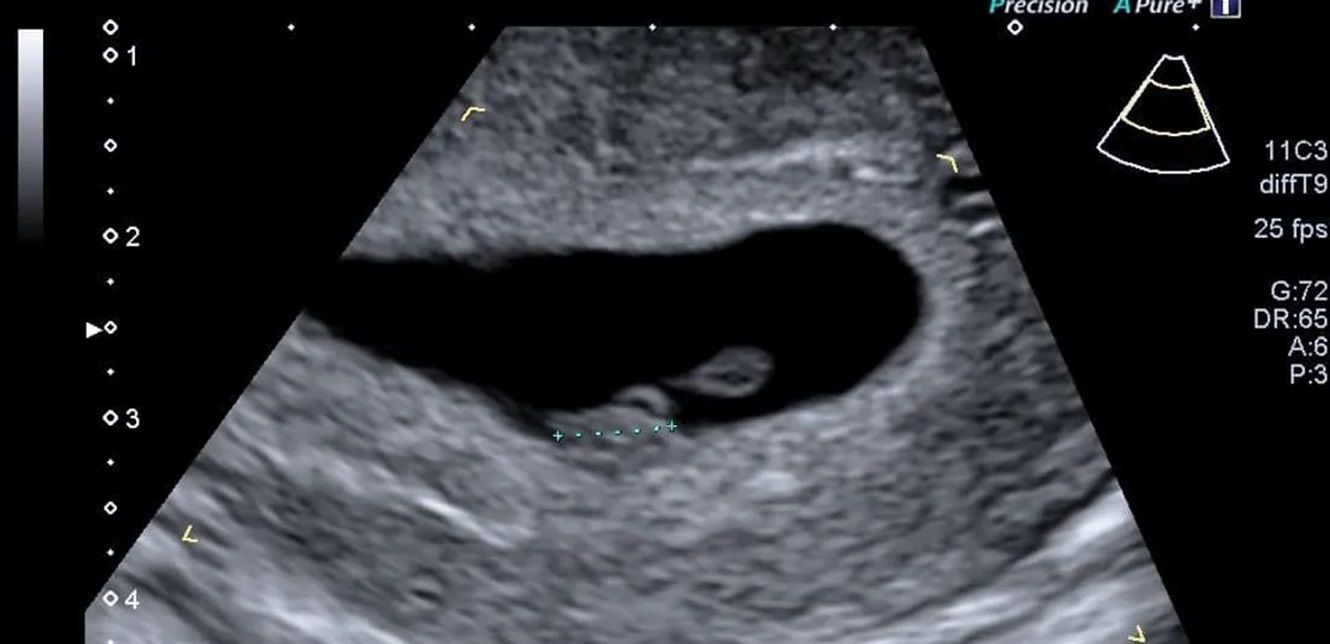

لكن مجموعة من الباحثين الأميركيين تقول إن استخدام الذكاء الاصطناعي لتحليل صور الموجات فوق الصوتية يمكن أن يتنبأ بموعد ميلاد الطفل بدقة تصل إلى 95 في المئة.

وباستخدام برنامج تم تطويره وتدريبه باستخدام أكثر من مليوني صورة بالموجات فوق الصوتية لنساء أنجبن أطفالهن بين عامي 2017 و2020، قام العلماء بقياس مدى قدرة الذكاء الاصطناعي على تقدير ما إذا كان الطفل سيرى النور في موعد ولادته أم لا.

أبرز نتائج البرنامج، المسمى Ultrasound AI:

التنبؤ بموعد ولادة الطفل في حالة الحمل المكتمل بدقة بلغت 95 في المئة.

التنبؤ بالولادة المبكرة بدقة بلغت 72 في المئة، من دون الحاجة إلى بيانات إضافية مثل التاريخ الطبي للأم أو القياسات السريرية.

التنبؤ بجميع حالات الولادة (بما في ذلك المبكرة) بدقة وصلت إلى 92 في المئة.

تعليقا على هذه النتائج، قال الدكتور جون أوبراين، مدير طب الأمومة والأجنة بجامعة كنتاكي: "الذكاء الاصطناعي بات يصل إلى داخل الرحم، ليساعدنا على التنبؤ بموعد الولادة بدقة، وهو ما سيقود إلى تحسين الرعاية الصحية للأمهات في جميع أنحاء العالم". (سكاي نيوزو)